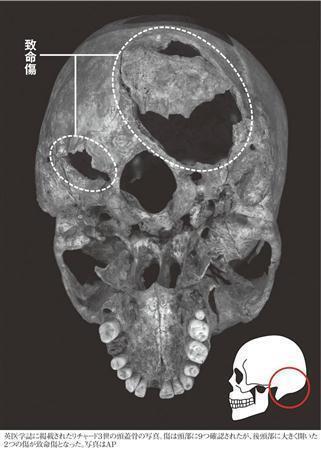

英医学誌に掲載されたリチャード3世(1452~85年)の頭蓋骨の写真。傷は頭部に9つ確認されたが、後頭部に大きく開いた2つの傷が致命傷となった(AP)

英医学誌に掲載されたリチャード3世(1452~85年)の頭蓋骨の写真。傷は頭部に9つ確認されたが、後頭部に大きく開いた2つの傷が致命傷となった(AP)【拡大】

遺骨の検視は英レスター大学の法医学チームが行い、17日の英医学誌「ランセット」に論文を発表した。英BBC放送(電子版)によると、CTスキャンを用い、少なくとも11カ所の傷を発見。そのうちのいくつかは死後に加えられた傷である可能性が大きいことが分かった。